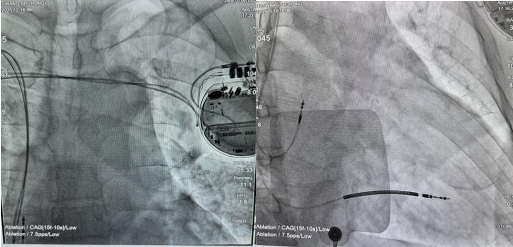

治疗方案确定,但一道罕见的“关卡”横在了手术团队面前。CT检查显示,屈老爷子存在“永存左上腔静脉”——锁骨下静脉直接连接冠状静脉,这种解剖变异的发生率仅约千分之三,给ICD精准植入带来极大挑战。“ICD对感知和除颤阈值要求极高,常规左侧植入路径因血管变异无法实施。”赵永辉主任医师介绍,团队结合两年前处理类似病例的经验,创新性制定了“右侧穿刺植入电极+胸骨前隧道牵引至左侧”的手术方案,同时启用“皮下电极导入器”这一“神器”,让跨胸骨牵引操作更安全顺畅。

术前反复推演,术中精准配合。在赵永辉主任医师的带领下,臧小彪副主任医师、赵智晗主治医师与王磊主治医师组成的手术团队默契协作,从穿刺、电极植入到隧道牵引,每一步都精准无误。历时1小时,手术顺利完成,ICD成功“上岗”守护老人心脏。